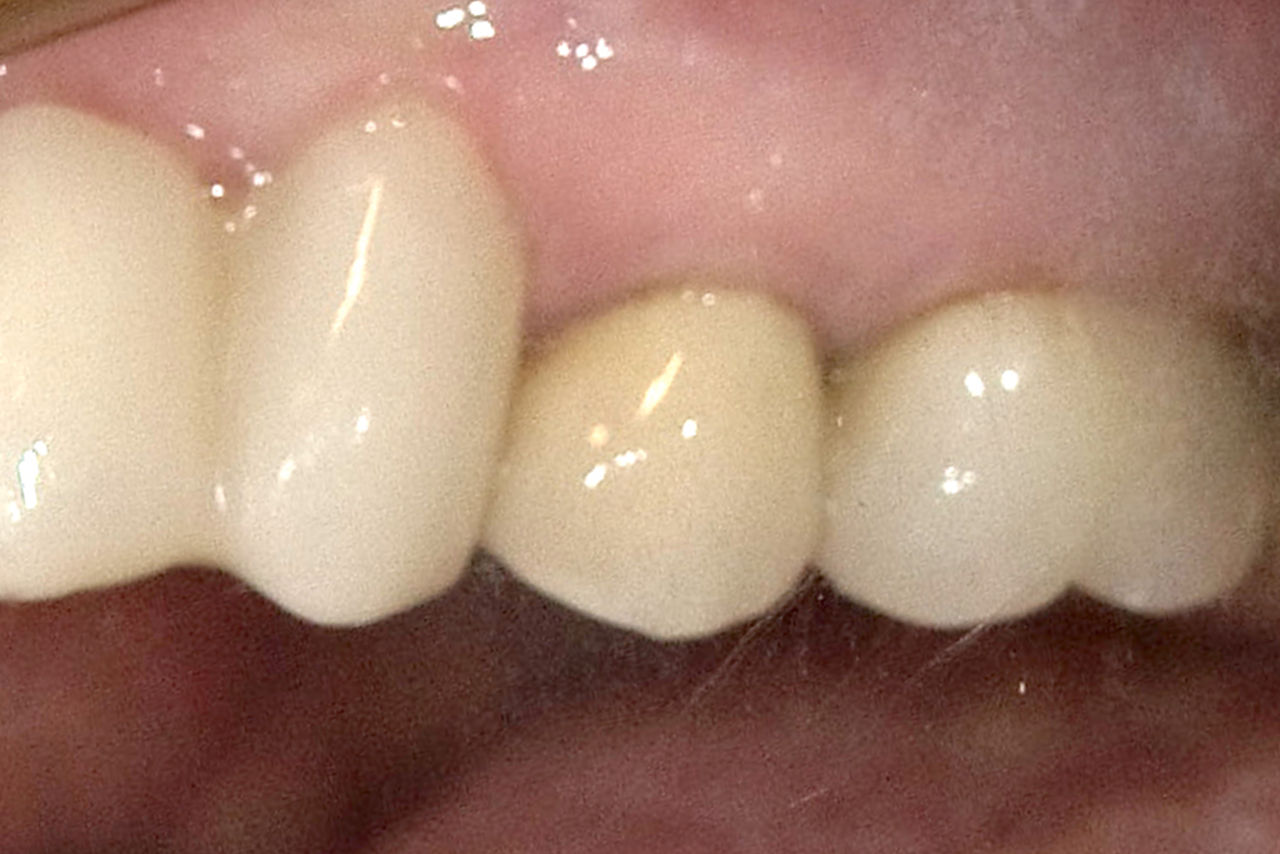

Después: Restauración fabricada chairside hecha de cerámica avanzada de disilicato de litio, CEREC Tessera.